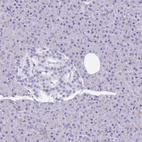

Immunohistochemistry analysis in human stomach and pancreas tissues using HPA052407 antibody. Corresponding GSDMB RNA-seq data are presented for the same tissues.